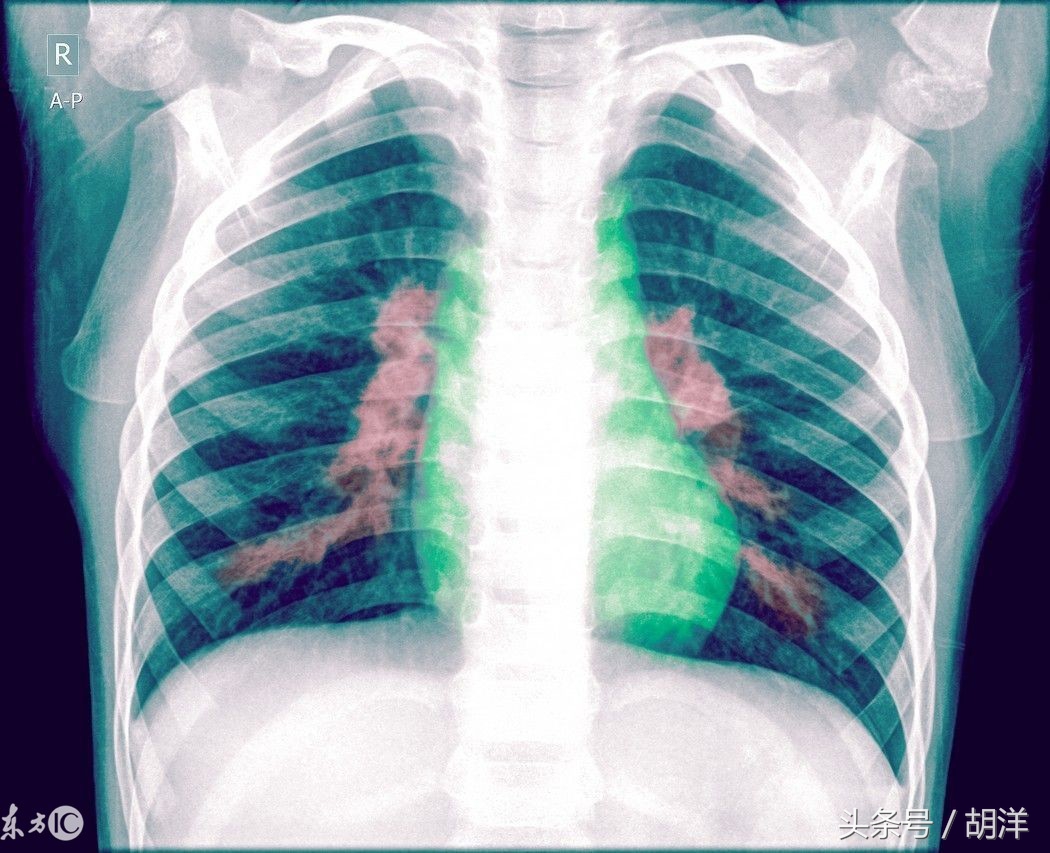

肺炎是内脏重要器官中最常见的一种感染性疾病

肺炎的症状多而复杂,根据不同的病原体和疾病的严重程度会有不同的表现,下面介绍一下肺炎的不同表现。